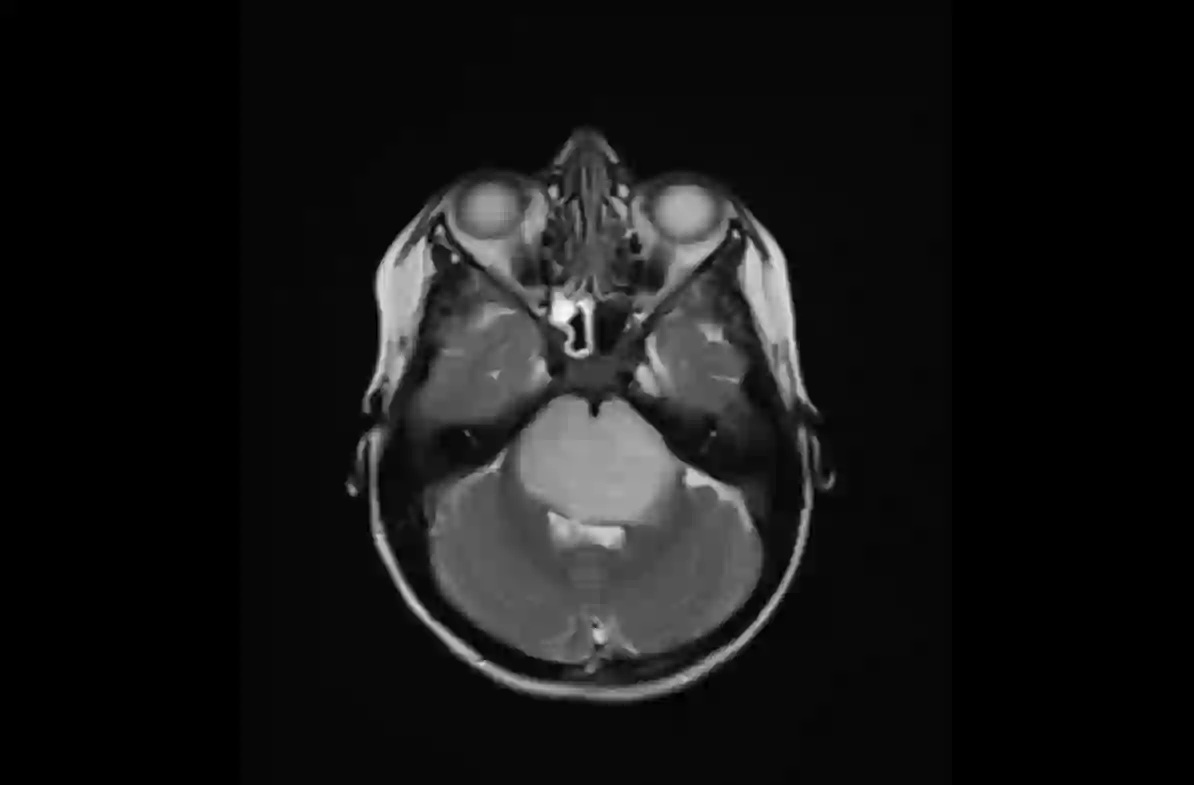

The field of explainability in artificial intelligence has witnessed a growing number of studies and increasing scholarly interest. However, the lack of human-friendly and individual interpretations in explaining the outcomes of machine learning algorithms has significantly hindered the acceptance of these methods by clinicians in their research and clinical practice. To address this, our study employs counterfactual explanations to explore "what if?" scenarios in medical research, aiming to expand our understanding beyond existing boundaries on magnetic resonance imaging (MRI) features for diagnosing pediatric posterior fossa brain tumors. In our case study, the proposed concept provides a novel way to examine alternative decision-making scenarios that offer personalized and context-specific insights, enabling the validation of predictions and clarification of variations under diverse circumstances. Additionally, we explore the potential use of counterfactuals for data augmentation and evaluate their feasibility as an alternative approach in our medical research case. The results demonstrate the promising potential of using counterfactual explanations to enhance trust and acceptance of AI-driven methods in clinical research.